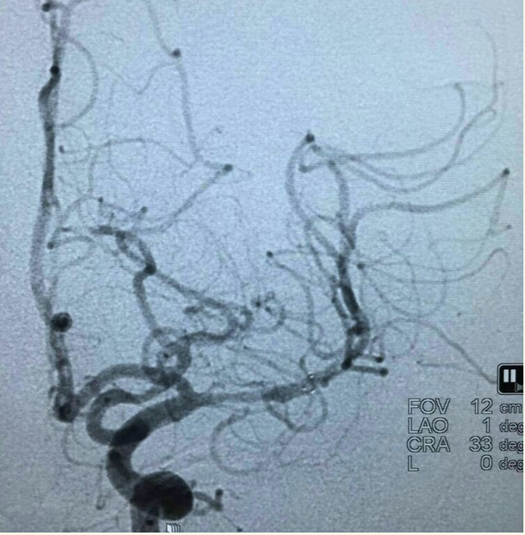

行球囊(gateway1.5*9)扩张: